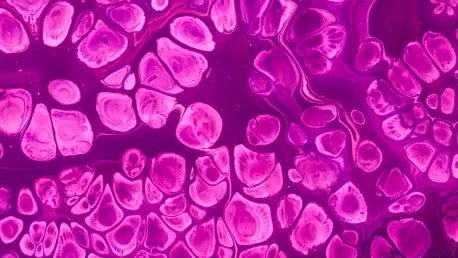

Der entscheidende chirurgische Durchbruch wurde durch die Anwendung einer neuartigen und in diesem Kontext weltweit einzigartigen Operationsmethode erzielt, die das etablierte Vorgehen revolutionierte. Während des hochkomplexen Eingriffs nutzte das chirurgische Team die extrakorporale Membranoxygenierung, besser bekannt unter der Abkürzung ECMO. Dieses System, das oft als künstliche Lunge bezeichnet wird, übernimmt temporär die vollständige Herz- und Lungenfunktion des Patienten außerhalb des Körpers. Durch die Ausleitung des Blutes, dessen Anreicherung mit Sauerstoff und die Entfernung von Kohlendioxid in einer Maschine wird der Kreislauf künstlich aufrechterhalten. Dies verschaffte den Chirurgen ein stabiles und kontrolliertes Operationsfeld sowie die nötige Zeit, den Tumor präzise und vollständig zu entfernen, was unter normalen physiologischen Bedingungen aufgrund der Lage und der Komplexität des Tumors undenkbar gewesen wäre.

Der Einsatz der ECMO in der onkologischen Chirurgie zur Behandlung eines Gallengangkarzinoms stellte eine absolute Premiere dar und demonstriert die Innovationskraft, die aus der engen Verknüpfung von klinischer Praxis und Spitzenforschung an der MHH entsteht. Diese bahnbrechende Technik war das Ergebnis einer perfekten Symbiose aus fortschrittlicher Pharmakotherapie, die den Tumor erst operabel machte, und einer revolutionären Operationstechnik, die den Eingriff selbst ermöglichte. Die drei Säulen dieses Erfolgs – herausragende medizinische Exzellenz, eine tief in der Forschung verankerte klinische Praxis und eine konsequent auf den Patienten ausgerichtete Haltung – schufen eine völlig neue Behandlungsoption. Für Susanne Viehmeier bedeutete dieser mutige und innovative Schritt nicht weniger als die realistische Perspektive auf ein Leben nach der Krebserkrankung, wo zuvor nur eine palliative Behandlung in Aussicht gestanden hatte.